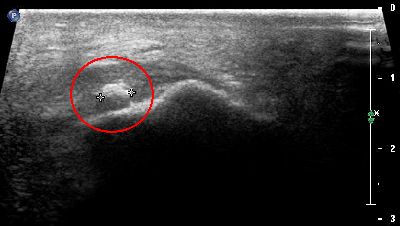

Calcificazione intra tendinea (img. 01) Calcificazione intra tendinea 01